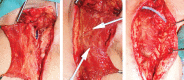

Background: Peripheral vascular surgery may be complicated by wound infection and potential graft exposure in the groin area. Muscle flap coverage of the graft has been promoted to address these wound complications. The authors present their findings regarding graft salvage rates and patient outcomes using local muscle flaps to address vascular graft complications of the groin.

Results: Seventeen patients undergoing local muscle flap coverage of a vascular graft were reviewed. Six men and 9 women, 51-80 years old, were included in the study. Wound complications in the groin occurred anywhere from 3 days to 3.5 years following graft placement. Graft exposure was the most common presenting complication (14 of 17 patients). Muscle flap coverage occurred within 15 days of complication presentation in all patients (average, 6.4 days). Seven of the 15 patients experienced postoperative complications within 6 months of the procedure, most commonly wound dehiscence. However, analysis demonstrated that vascular grafts were successfully salvaged in 10 of the 17 patients (59%) over the course of follow-up (range, 104-1748 days). Average time to muscle flap coverage was 4.2 days in patients who retained the graft and 9.6 days in patients who ultimately lost their vascular graft.

Conclusion: The authors demonstrate improved vascular graft salvage rate when local muscle flap procedure is performed early after initial wound complication presentation.